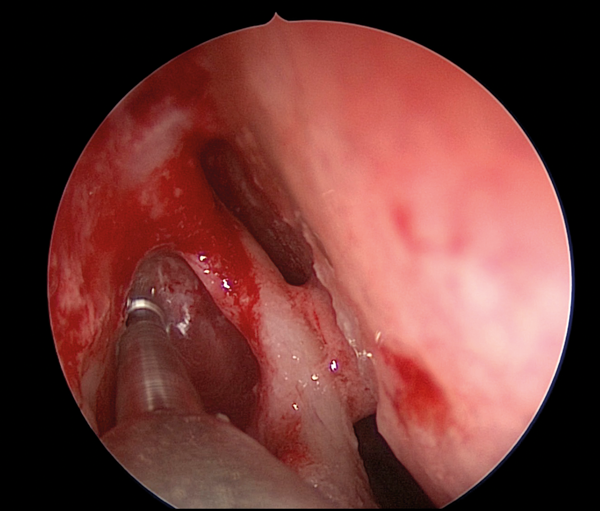

Figure 3. Initiating anterior lacrimal sac incison.

The medial wall of the sac is tented medially using the end of the O’Donaghue probe and incised vertically using a sharp pointed Phaco knife at its most anterior aspect (see Figure 3). The aim is to create a large posterior based sac flap, which can later be folded back towards the uncinate process, facilitating full sac marsupialisation. Relieving incisions are then placed horizontally, both superiorly (see Figure 4) and inferiorly (see Figure 5) to complete the sac incision into a ‘C’ shape. The remaining posterior edge is left intact but the completed sac wall flap can now be folded posteriorly, exposing the entire sac lumen. The lacrimal probe should be visible and is pulled through with Mosquito artery forceps. The process is repeated with the probe and stent through the superior canaliculus. Upon delivery of the stents a Watzke sleeve is placed and the stents are tied. The lacrimal sac flaps remain folded backwards but the nasal mucosal flaps are repositioned to overlap each sac flap to encourage healing and ensure there is no exposed bone (see Figure 6).